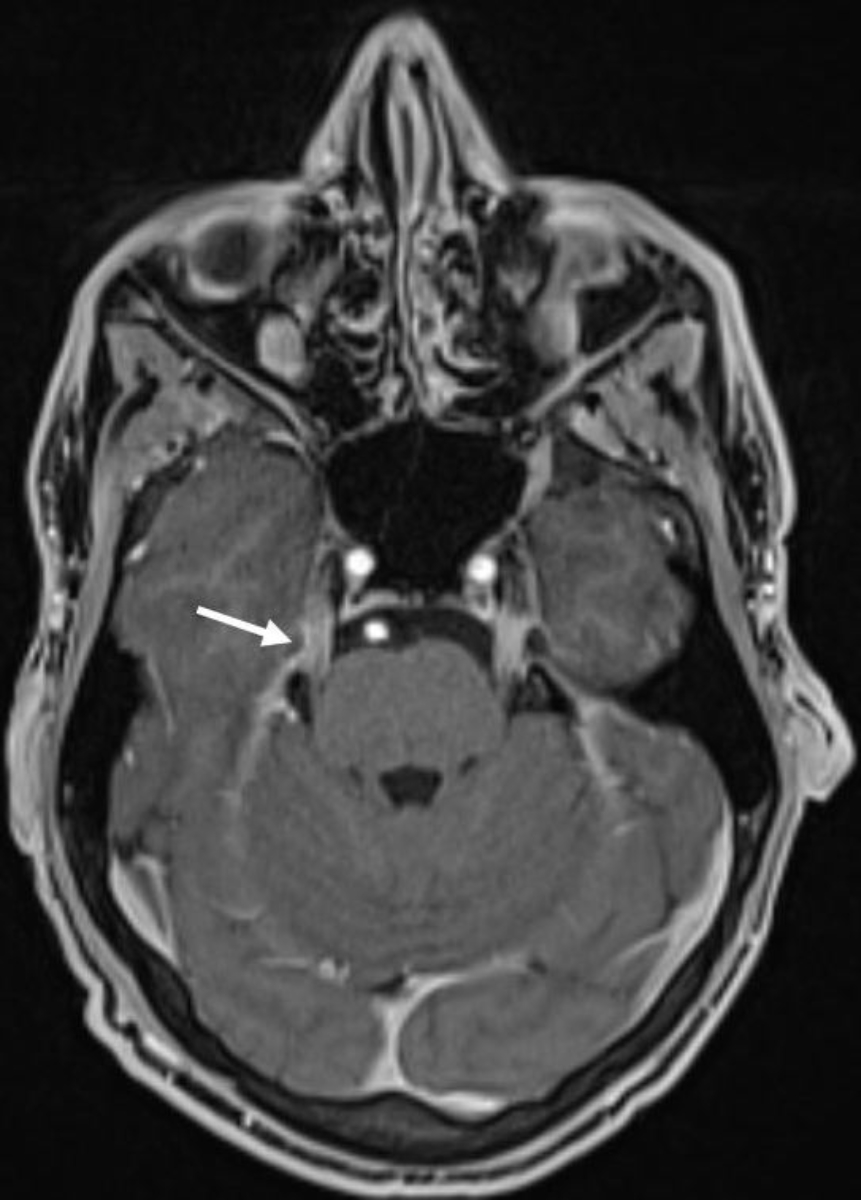

The second dose of ANV419 was given as planned and at the same dose two weeks after tumour-infiltrating lymphocyte transfer. Subsequently, the patient reported an increasing worsening of the previously present sensory polyneuropathy of the hands and feet, as well as new distal muscle weakness. Muscle weakening was measurable as a new distal paresis of both feet: foot elevation: 3/5, foot drop: 4/5, big toe elevation: 3/5, toe elevation: 3/5, according to the Medical Research Council (MRC) Scale (Grade 5: normal, Grade 4: movement against gravity and resistance, Grade 3: movement against gravity over the full range, Grade 2: movement of the limb but not against gravity, Grade 1: visible contraction without movement of the limb, Grade 0: no visible contraction). The patient developed an increasingly ataxic gait. Heel and toe gait was not possible. Both feet showed pall-hypoaesthesia, tested with 128 Hz-Diapason with result 4/8 (scale for assessment of disorders of vibratory sensitivity, range 0 to 8, with 8 being intact vibratory sensitivity). Furthermore, the muscle reflexes were absent bilaterally. A brain and spine MRI excluded the presence of central nervous system metastases but revealed a diffuse pathological contrast enhancement of the intraspinal nerves from cervical to sacrum including the cauda equina as well as a symmetrical pathological contrast enhancement of several cranial nerves on both sides. This finding was primarily compatible with the established diagnosis of chronic inflammatory demyelinating polyneuropathy (figures 2 and 3).

Figure 3Brain MRI (T1 VIBE with gadolinium): symmetrical pathological contrast enhancement of several cranial nerves on both sides (N. trigeminus in the picture, N. oculomotorius, N. facialis) primarily compatible with the diagnosis of chronic inflammatory demyelinating polyneuropathy (CIDP).